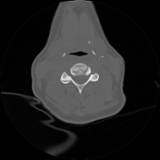

Acute calcific deposit on the enthesis of the longus colli muscle

The severe cervical spine pain prompted an emergency MRI examination, which showed a clear prevertebral inflammatory soft tissue process. On close inspection, a calcific deposit anterior to the dens axis can already be suspected on MRI (especially T2 or axial T1fs Gd+). The calcium depot is only shown very fluffy on X-ray and CT, suggesting an acute stage with precipitation/resorption of the calcific milk.

The longus colli muscle is a less common location of this condition, which should be referred to as HADD or acute calcific deposit. Also affected may be supraspinatus tendon and other tendons of the rotator cuff, extensor carpi radialis tendon, deltoid muscle, or hip adductors.